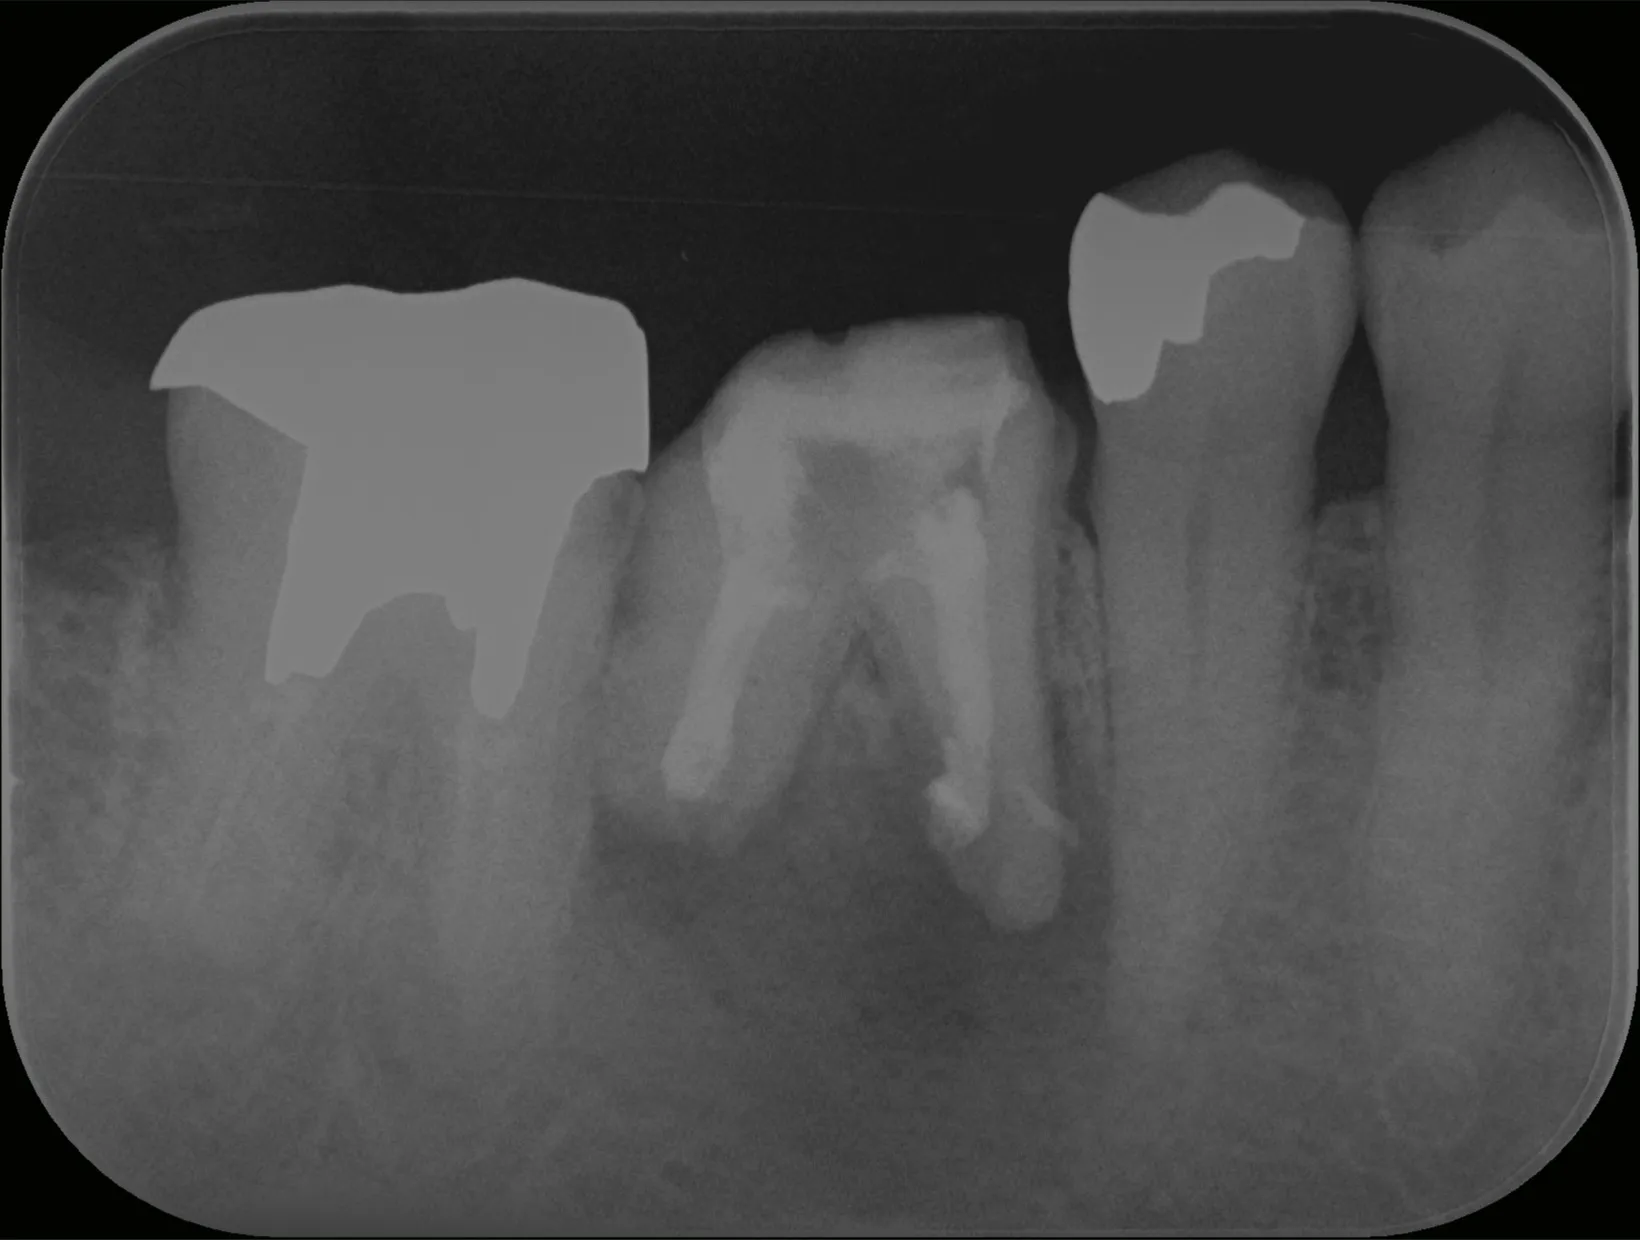

今回は抜歯になってしまった歯からインプラント治療完了までの流れについてご紹介いたします。